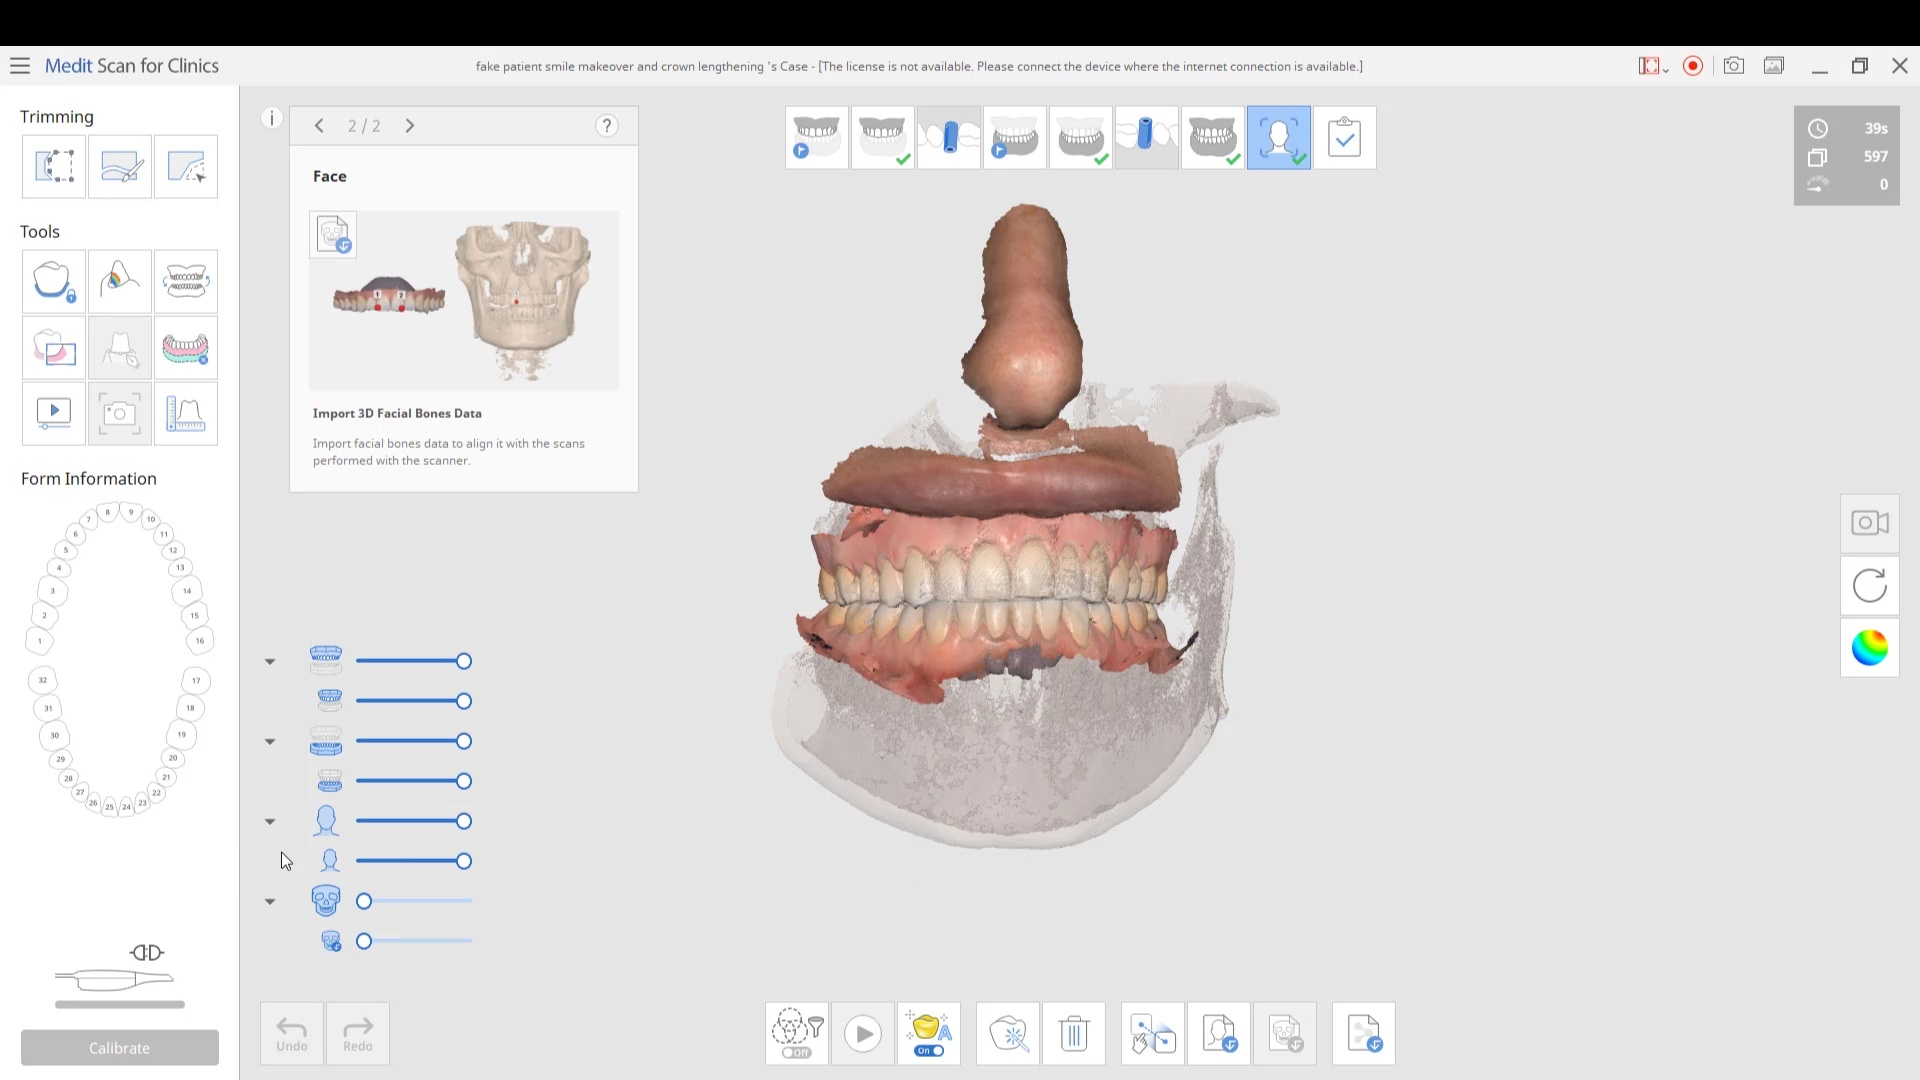

Using the CT as a Remount Jig If You Have Lost The Vertical Dimension For Some Reason or Another

November 20, 2020At CAD-Ray, we have now designed over 20,000 implant cases since 2013. One of the most common requests we get is from doctors doing full arches and their desires to […]